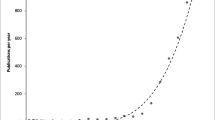

We measured the tensile properties of each specimen according to material type, the number of silicone coatings, and hardness (Table 2, Fig. 2). Table 2 lists the tensile strengths and elongations of three materials according to the number of silicone coatings (0, 2, or 8) and the associated uncertainties. The tensile strengths and elongations of the three materials were significantly different when the number of silicone coatings was the same based on the Kruskal–Wallis test (p < 0.05) except for the tensile strength results between the Agilus and Elastic (2 times, p = 0.31; 8 times, p = 0.84) based on Wilcoxon signed-rank test. Figure 2A,B show the trends of increases in tensile strength and decreases in elongation of the specimens with an increase in material hardness derived from the vendors’ reference measurements. Ratios of Vero in the Agilus and Vero combinations from 0 to 50 have positive association with hardness values. As hardness increased, tensile strength increased and elongation decreased. These results might not show significant differences in tensile strength at the same hardness condition based on the Wilcoxon signed-rank test (A-V vs. Elastic at 50 Shore A, p = 0.86; A-V vs. Flexa at 60 Shore A, p = 0.15), whereas significant differences in elongation were seen in the same hardness condition based on the Wilcoxon singed-rank test (A-V vs. Elastic at 50 Shore A, p < 0.05; A-V vs. Flexa at 60 Shore A, p < 0.05). Figure 2C,D presented tensile strengths and elongation from three materials in accordance with the number of silicone coatings (0, 2, 8 times). The tensile strength of the materials did not change significantly with the number of silicone coatings (Fig. 2C). Figure 2D shows that the elongation of only the Agilus increased significantly with the number of silicone coatings, whereas those of the Elastic and Flexa did not differ significantly with different number of silicone coatings based on the Mann–Whitney U test (Agilus, p < 0.05; Flexa, p = 0.13; Elastic, p = 0.65).

The mechanical properties of specimens with various hardness degrees and numbers of silicone coatings. Four different composites of the Agilus with Vero (A-V) were printed to control for hardness value of 30, 40, 50, 60 Shore A (A): tensile strength [MPa]; (B): elongation [%]). The mechanical properties are presented according to the number of coatings for all three materials (C): tensile strength [MPa]; (D): elongation [%]). The plots were drawn using R packages dplyr and ggplot2.